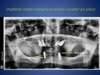

Prothèse complète amovible inférieure stabilisée sur 2 implants (Boule)